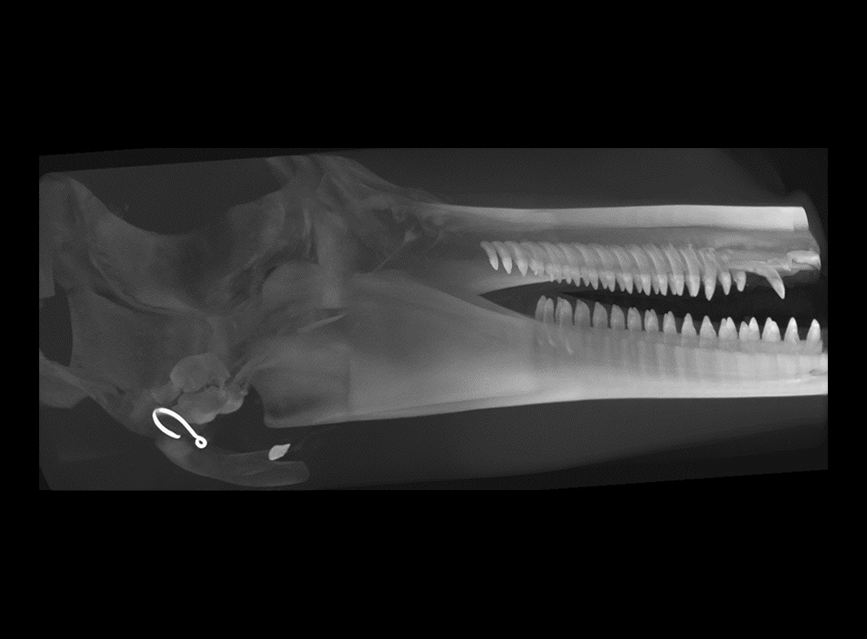

Our High Definition Volumetric Imaging (HDVI) technology is the most advanced form of Flat Panel CT technology. It delivers high-quality diagnostic imaging for both hard and soft tissues. This technology includes specific presets and customizable accessories designed for aquatic animals.

High Definition Volumetric Imaging (HDVI) Computed Tomography and Fluoroscopy in one device.

Outstanding image quality in hard and soft tissues with a spatial resolution up to 100 μ.